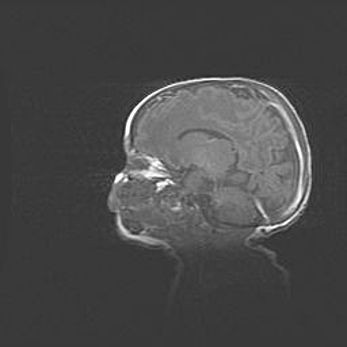

Наружная гидроцефалия с возможной атрофией височных областей.

Возраст: 28 дней

Вес: 3670 г

Пол: мужской

Окружность головы: 38 см

Срок гестации: 40 недель

Гидроцефалия головного мозга у новорожденных – это заболевание, которое характеризуется скоплением избыточного количества спинномозговой жидкости в желудочковой системе головного мозга в результате затруднения её перемещения от места выработки к месту поглощения в кровеносную систему или вследствие нарушения абсорбции. При открытой наружной форме гидроцефалии у новорожденных расширяются и переполняются субарахноидные пространства.

При нормотензивных  формах,  которые,  как  правило,  являются  следствием  перенесенных ишемических  повреждений  паренхимы  мозга,  возможно  сочетание микроцефалии  с нормотензивной гидроцефалией. В основе данных изменений лежит атрофия больших полушарий с преимущественной  локализацией  в  лобно-височных  областях.